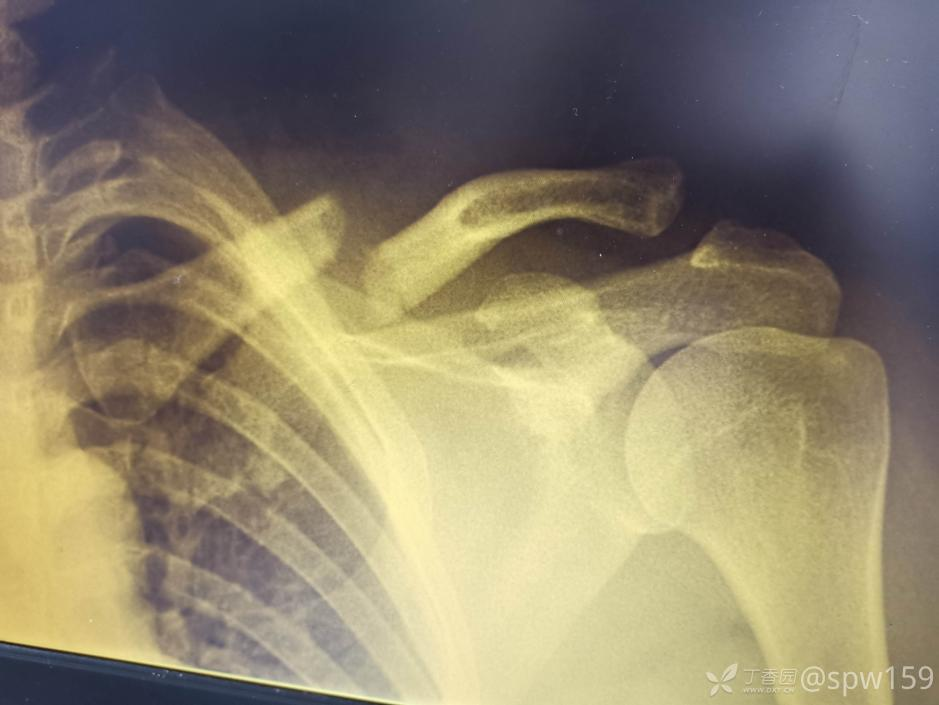

锁骨骨折大家一定都觉得很简单,但锁骨骨折也有一个并不少见的坑,看看下面的病例:

这个锁骨骨折简单吗?简单!做不就完了吗?

做完了,骨折解剖复位漂亮吧?干得漂亮!等等!怎么肩锁关节脱位了 ……

这个锁骨骨折简单吗?另一位网友分享:

等下,拍个双侧对比看看,锁骨骨折合并肩锁关节脱位,还好术前发现了 ……

这样的病例少吗?还真不少,一搜一大把!

6.8% 的锁骨中段骨折患者伴有同侧肩锁关节脱位。这个坑也不能踩啊!